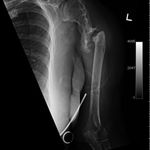

Some time in late May 2010, she presented with movement of the fracture site and was noted that the central area of healing had broken down and was thought that she had a deep infection. She was taken back to theater in mid June 2010 when operation showed that there was no pus. Multiple samples of the fracture site were taken and an external fixator applied with compression of the fragments. Following that, the cultures taken from the wounds showed no growth and no organisms and a biopsy showed no sign of any malignancy or abnormal cells. The fixator became loose and eventually had to be removed. This was done in July 2010 and she was discovered to be going onto a hypertrophic nonunion. Low dose ultrasound treatment of the fracture site was tried to help stimulate healing over the course of a few months but the non union persisted.